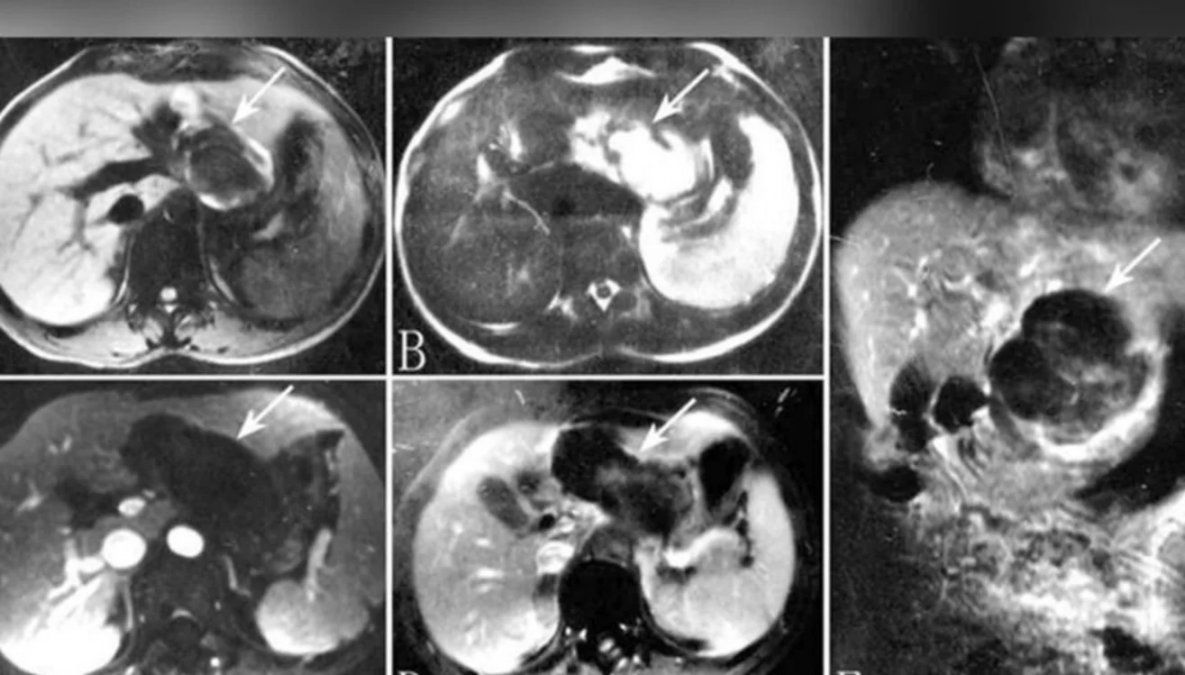

Entonces se procedió a hacerle un ecografía que reveló que había un bebé en su hígado.

Tenía una versión extremadamente rara de un embarazo ectópico, en el que "un óvulo fertilizado se implanta y crece fuera de la cavidad principal del útero", de acuerdo con los datos de la Clínica Mayo.

Sin embargo, el caso de esta paciente era aún más raro, ya que el embrión "acabó viajando hasta el hígado, donde se implantó", señaló el médico.